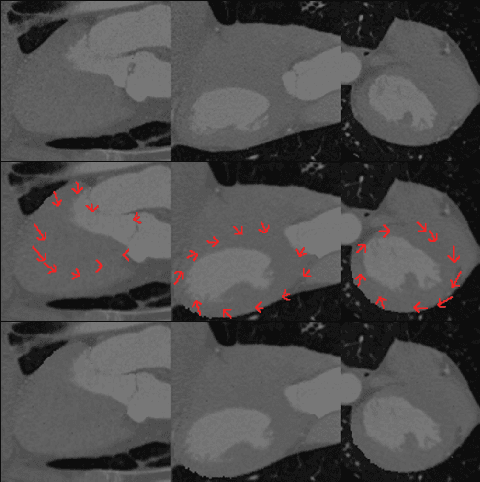

Abstract:The ability to map left ventricle (LV) myocardial motion using computed tomography angiography (CTA) is essential to diagnosing cardiovascular conditions and guiding interventional procedures. Due to their inherent locality, conventional neural networks typically have difficulty predicting subtle tangential movements, which considerably lessens the level of precision at which myocardium three-dimensional (3D) mapping can be performed. Using 3D optical flow techniques and Functional Maps (FMs), we present a comprehensive approach to address this problem. FMs are known for their capacity to capture global geometric features, thus providing a fuller understanding of 3D geometry. As an alternative to traditional segmentation-based priors, we employ surface-based two-dimensional (2D) constraints derived from spectral correspondence methods. Our 3D deep learning architecture, based on the ARFlow model, is optimized to handle complex 3D motion analysis tasks. By incorporating FMs, we can capture the subtle tangential movements of the myocardium surface precisely, hence significantly improving the accuracy of 3D mapping of the myocardium. The experimental results confirm the effectiveness of this method in enhancing myocardium motion analysis. This approach can contribute to improving cardiovascular diagnosis and treatment. Our code and additional resources are available at: https://shaharzuler.github.io/CardioSpectrumPage

Abstract:Accurate analysis of 3D myocardium deformation using high-resolution computerized tomography (CT) datasets with ground truth (GT) annotations is crucial for advancing cardiovascular imaging research. However, the scarcity of such datasets poses a significant challenge for developing robust myocardium deformation analysis models. To address this, we propose a novel approach to synthetic data generation for enriching cardiovascular imaging datasets. We introduce a synthetic data generation method, enriched with crucial GT 3D optical flow annotations. We outline the data preparation from a cardiac four-dimensional (4D) CT scan, selection of parameters, and the subsequent creation of synthetic data from the same or other sources of 3D cardiac CT data for training. Our work contributes to overcoming the limitations imposed by the scarcity of high-resolution CT datasets with precise annotations, thereby facilitating the development of accurate and reliable myocardium deformation analysis algorithms for clinical applications and diagnostics. Our code is available at: http://www.github.com/shaharzuler/cardio_volume_skewer